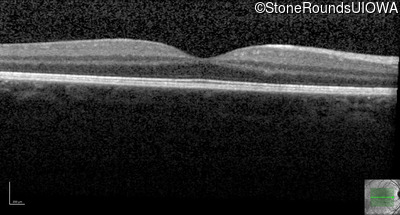

Optical Coherence Tomography - Left - 20/20 -1

Exemplar / OCT Stack